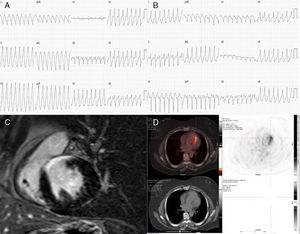

A) TV1: TV con longitud de ciclo de 290ms, morfología de bloqueo de rama izquierda (QRS 180ms), eje inferior derecho y disociación VA. B) TV2: TV con longitud de ciclo de 280ms, morfología de bloqueo de rama izquierda (QRS 120ms), eje superior izquierdo y disociación VA. C) Secuencias de realce tardío con gadolinio en la CRM. D) Hipercaptación con 18F-FDG de PET/TC toracoabdominal.

Mujer de 59 años con antecedentes de hipertensión arterial, diabetes mellitus tipo 2, dislipemia e hipotiroidismo. Además, padece una artritis psoriásica grave tratada con deflazacort y etanercept. Es derivada a nuestro centro para estudio electrofisiológico por taquicardia regular de QRS ancho, bien tolerada clínica y hemodinámicamente, con sospecha de origen supraventricular y conducción aberrante, sin cardiopatía estructural aparente. El electrocardiograma basal con ritmo sinusal, bloqueo auriculoventricular de primer grado (PR de 210ms) y bloqueo incompleto de rama izquierda (QRS 110ms). Con trenes de estímulos e infusión de isoproterenol se inducen 2 taquicardias ventriculares (TV): TV1 con longitud de ciclo de 290ms, morfología de bloqueo de rama izquierda (QRS 180ms), eje inferior derecho y disociación VA (fig. 1A) y TV2 con longitud de ciclo de 280ms, morfología de bloqueo de rama izquierda (QRS 120ms), eje superior izquierdo y disociación VA (fig. 1B), esta última idéntica a la taquicardia clínica. Ambas TV ceden de manera espontánea. Estos datos son compatibles con TV de posible mecanismo automático o actividad triggered en relación a una cardiopatía estructural aún no identificada, por lo que se decide finalizar el estudio.

Un ecocardiograma muestra un movimiento septal asincrónico con aquinesia y discreto adelgazamiento anteroseptal basal y fracción de eyección del ventrículo izquierdo del 55%. Se descarta enfermedad arterial coronaria mediante una angiografía coronaria. Se realiza cardiorresonancia magnética (CRM) evidenciándose en las secuencias de realce tardío con gadolinio captación transmural a nivel anteroseptal basal y medio y en el segmento inferior basal (fig. 1C). La localización de una distribución no coronaria de la cicatriz en la CRM, nos planteó el diagnóstico diferencial entre entidades como la miocardiopatía arritmogénica, la miocarditis o la sarcoidosis cardiaca (SC). La falta de otros criterios asociados de miocardiopatía arritmogénica, tanto de imagen como electrocardiográficos, y la ausencia de antecedentes de miocarditis nos hicieron profundizar en la sospecha diagnóstica de SC. Se realiza una tomografía con emisión de positrones/TC con 18F-fluorodesoxiglucosa (18F-FDG PET/TC) de tórax y abdomen (tras retirada de corticoides prescritos por la artritis psoriásica) que muestra hipercaptación cardiaca de carácter parcheado a nivel del septum en su porción más anterior y en la región basal de la cara inferoseptal (fig. 1D), sin captación en otros órganos. Estos hallazgos se consideraron compatibles con el diagnóstico de una posible SC. Se descartó cualquier tipo de afectación extracardiaca mediante tomografía computarizada de tórax de alta resolución. No se realizó biopsia cardiaca.